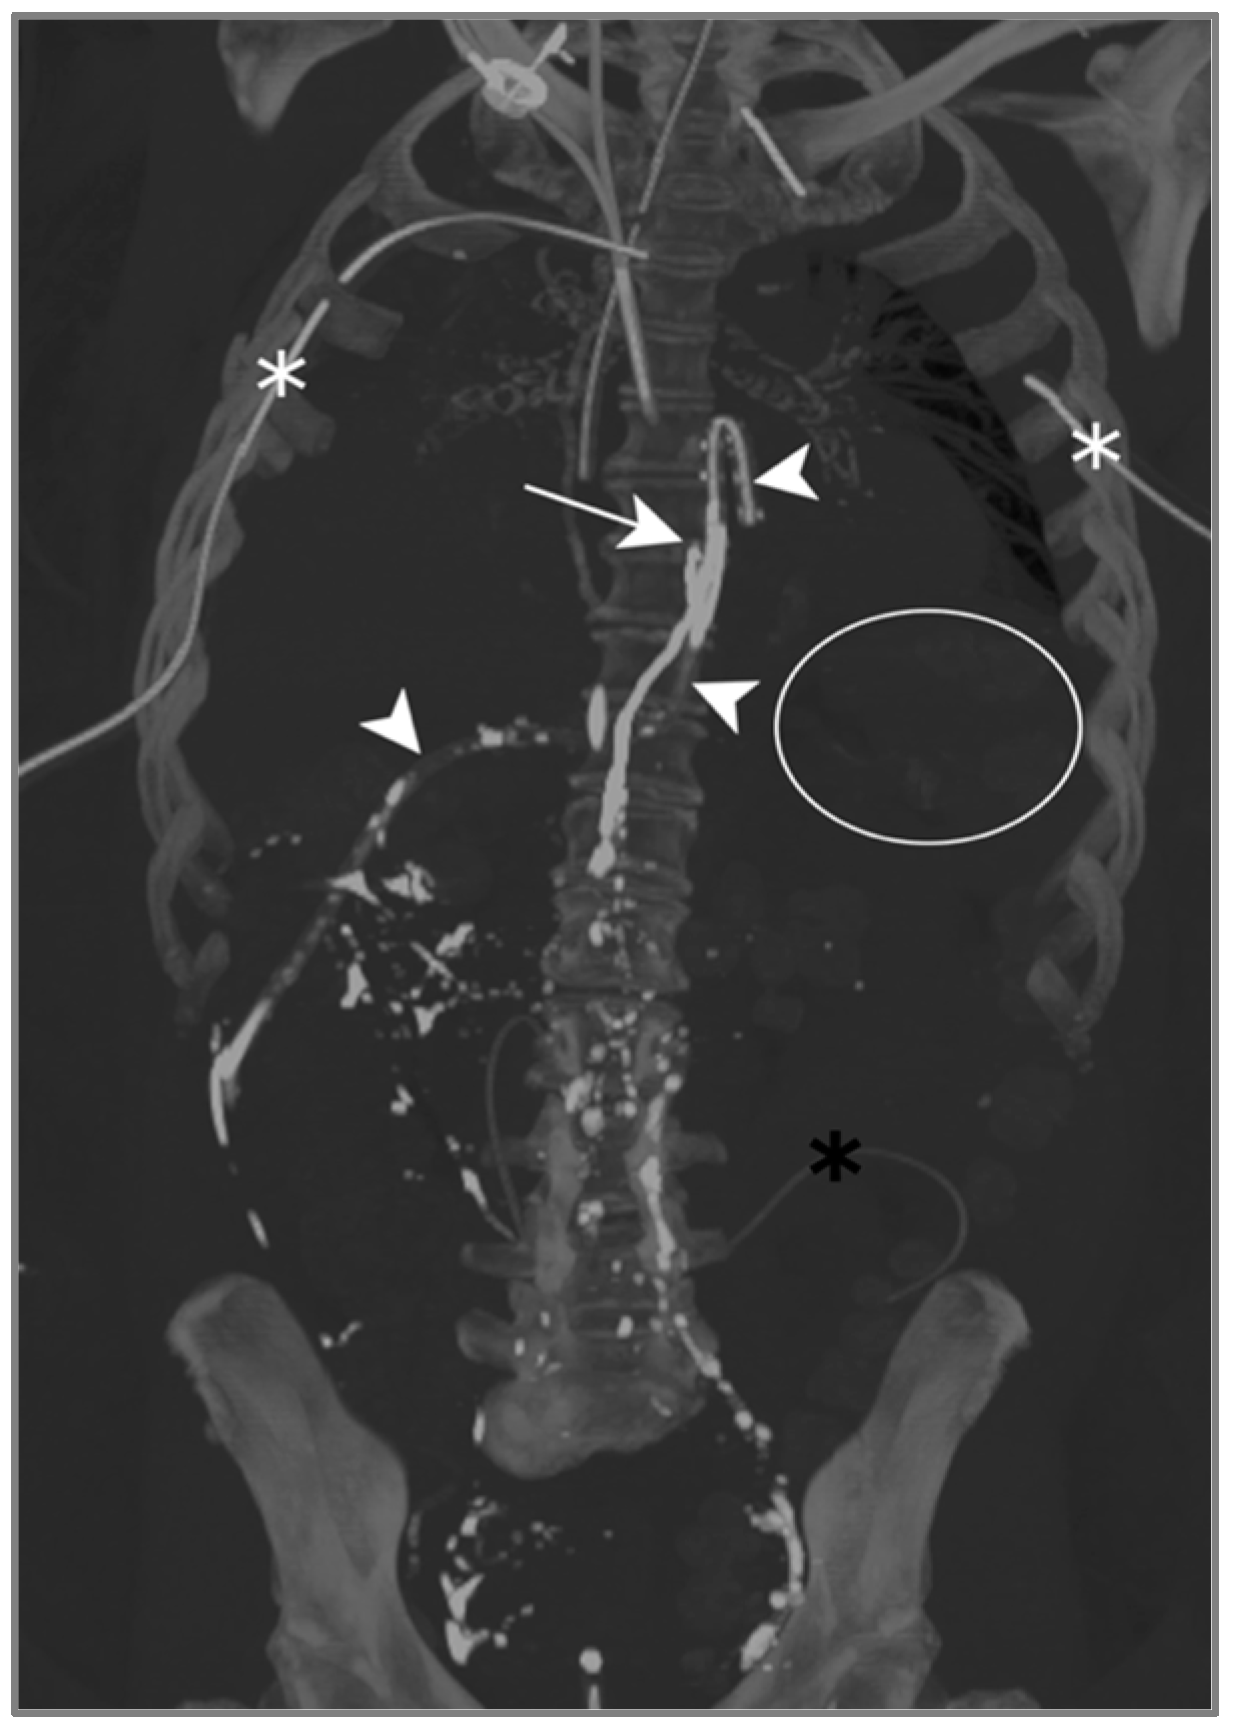

The contrast injected in the inguinal region showed ascension into the thoracic duct up to the level of the inferior vertebral plateau of D7, as well as the leakage and accumulation of Lipiodol in both pleural spaces: Lipiodol also accumulated in the drain coming into contact with the esophago-jejunal anastomosis (Figure 5).

Figure 5.

Patient A. The maximal-intensity projection of the CT scan reconstructed in the coronal plane. The Lipiodol injection shows opacification of the left inguinal and prevertebral lymphatic chains up to the level of the inferior vertebral plateau of D7 (white arrow). The drainage of the contrast agent through the catheter along the oesophagojejunal anastomosis is highlighted (white arrowheads). The subtle soft attenuation in the projection of the left lung field (white circle) corresponds to the accumulation of contrast in the pleural space due to the lymphatic rupture. The bilateral pleural catheter (white asterisks) and peritoneal drain (black asterisk) are identified.

One day after lymphangiography, the drain output had diminished by half, and reduced to less than 100 mL/d as of day 2. Per-mouth nutrition was begun progressively, with no recurrence of chylous effusion, allowing for drain removal on day 13.

Lymphangiography was therefore successful in treating this bilateral post-operative chylothorax.